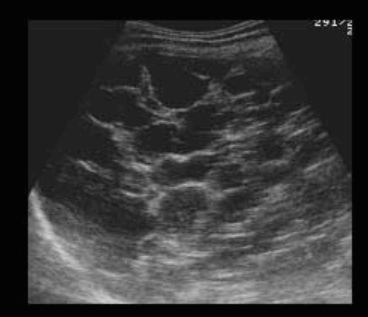

상염색체 우성 다낭성 간질환이라고도 불리는 다낭성 간질환은 유전성 질환이다. 간전체에 흩어져 있는 다양한 크기의 낭종의 점진적인 성장이 특징이다. 이 상태의 영향을 받은 사람들은 나이가 들어감에 따라 점점 더 큰 낭종을 갖는 경향이 있으며 보통 30세부터 증상이 나타나기 시작한다. 그러나 많은 영향을 받은 사람들은 증상이 없다. 대부분의 경우는 상염색체 우성으로 유전되지만, 일부는 가족력이 없는 가정에서도 발생한다. ADPKD를 가진 대부분의 사람들은 간낭종을 가지고 있다.

US finding

- 다양한 크기로 다발성

- 다수 발생 시 간종대 발생

- 60~70% 다낭성 신질환과 동반된다

- 낭종벽에 석회화 동반

- 격막이 형성되어 있다

polycystic liver disease ③ bile duct hamartomas